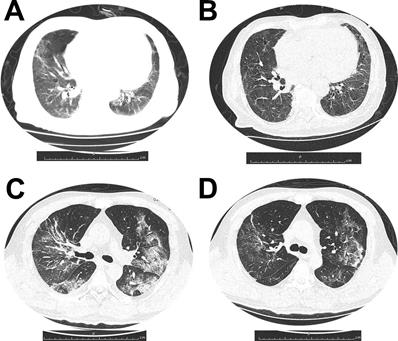

All patients had abnormal chest radiograph and the common abnormities on imaging were ground-glass opacities. Figure 1 demonstrated dynamic CT changes of one survivor and one non-survivor during the clinical course of SARS-CoV-2 infection.

Figure 1

(A and B) Dynamic changes of chest CT images from a 79-year-old man who survived the disease. (A) Bilateral ground-glass opacity and consolidation with interlobular septal thickening on day 10 after symptom onset. (B) After 11 days treatment, chest CT scan from the man showed pulmonary infiltration was absorbed largely. (C and D) Chest CT images from a 53-year-old woman with severe pneumonia, who died for multiorgan failure. (C) Multiple ground-glass opacities and consolidation in both sides of lungs, on day 15 after symptom onset. (D) After 7 days treatment, chest CT image of the woman showed pulmonary infiltration was partially absorbed.

The chest CT images from a 79-year-old man who survived the disease showed the bilateral ground-glass opacity and consolidation with interlobular septal thickening on day 10 after symptom onset. And after 11 days treatment, chest CT scan from the man showed pulmonary infiltration was absorbed largely. Chest CT images from a 53-year-old woman with severe pneumonia, who died for multiorgan failure showed multiple ground-glass opacities and consolidation in both sides of lungs, on day 15 after symptom onset. After 7 days treatment, chest CT image of the woman showed pulmonary infiltration was still existed.